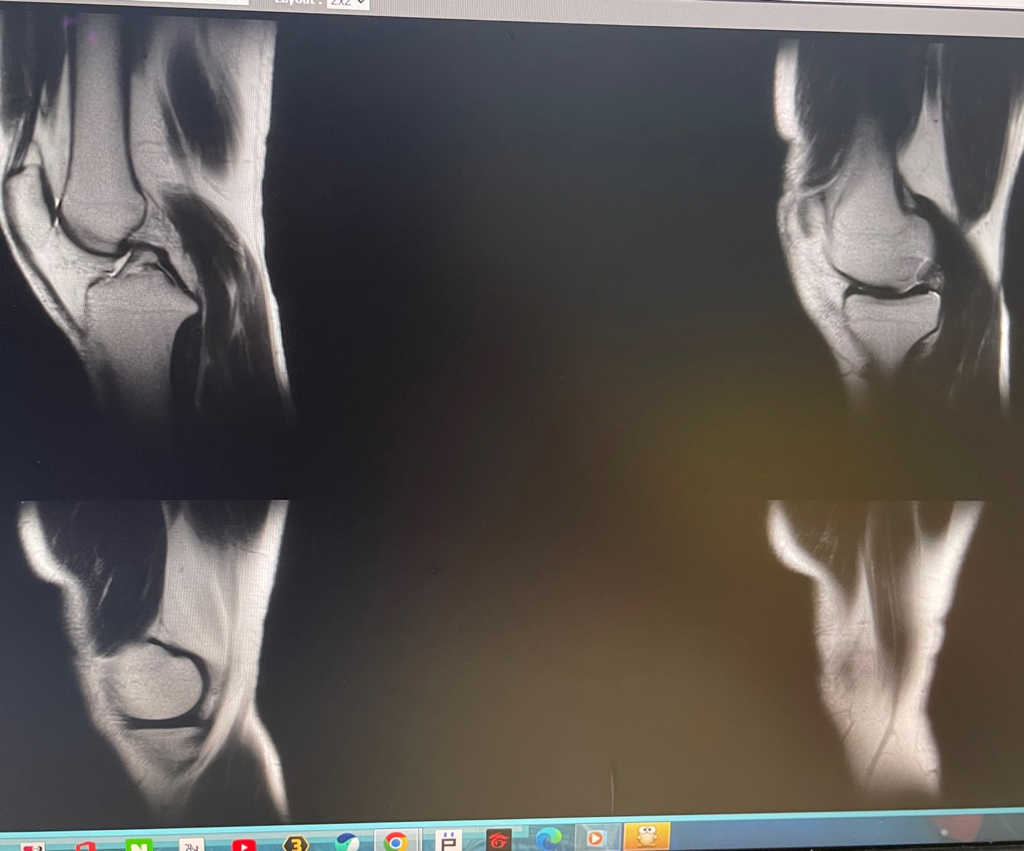

무릎 mri 원형원골인지 봐주실 수 있을까요

무릎이 너무 자주 아파서 mri를 찍어봤는데 무릎 연골에 이상이 있을까요

무릎이 선천적으로 원형연골인지 봐주시면 감사하겠습니다

MRI 판독에는 퇴행성 연골 손상, 바깥쪽 원판형 반월상 연골 이 의심된다고 적혀 있습니다.